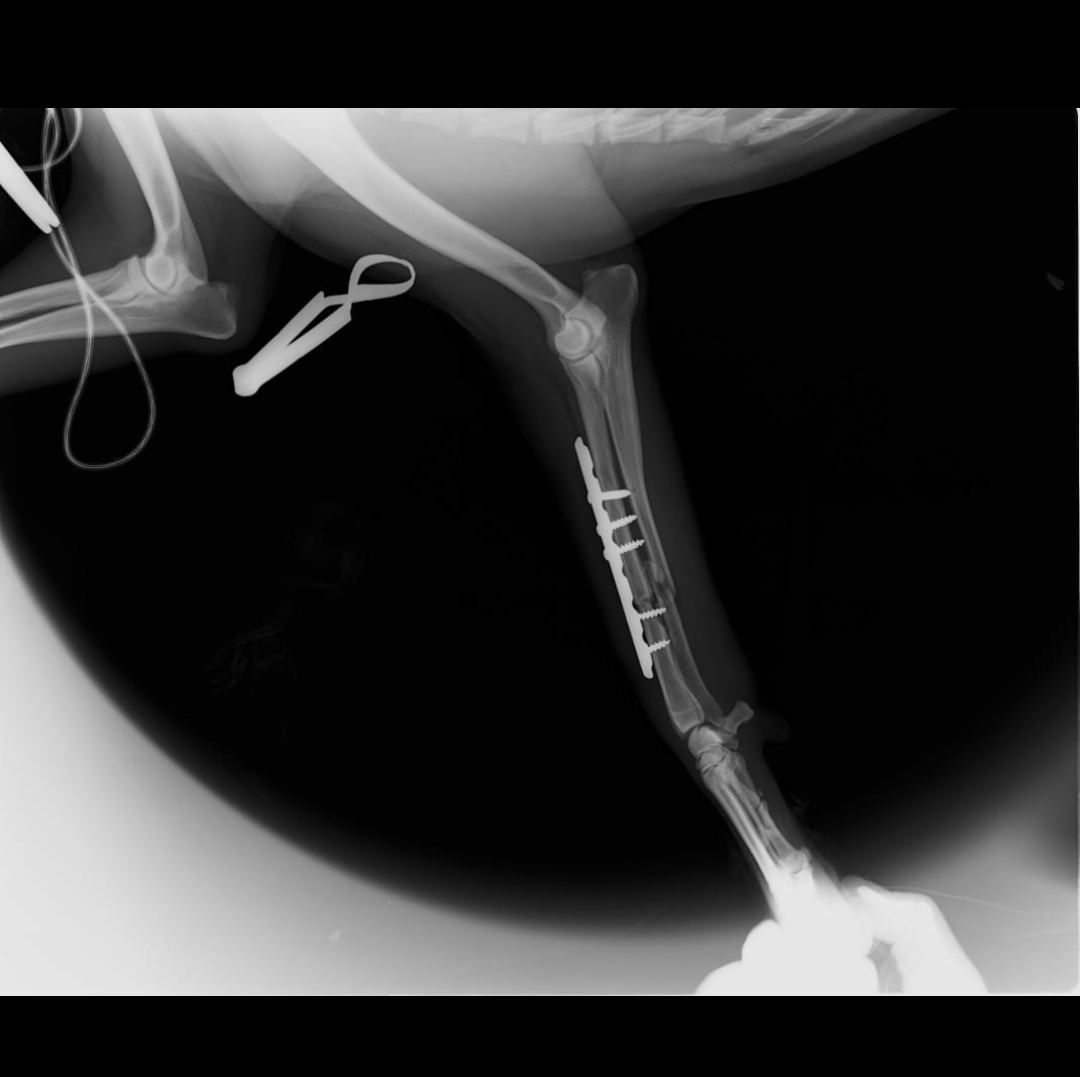

Amber had her surgery on the 14th of July. The surgery went well. She now has a plate inserted in her leg.

Here is her Xray and blood reports and a smiling Amber for you all. Please keep her in your prayers and send her healing vibes. A huge huge thank you to each one of you who donated for this sweet sweet girl โค๏ธ๐๐งฟ